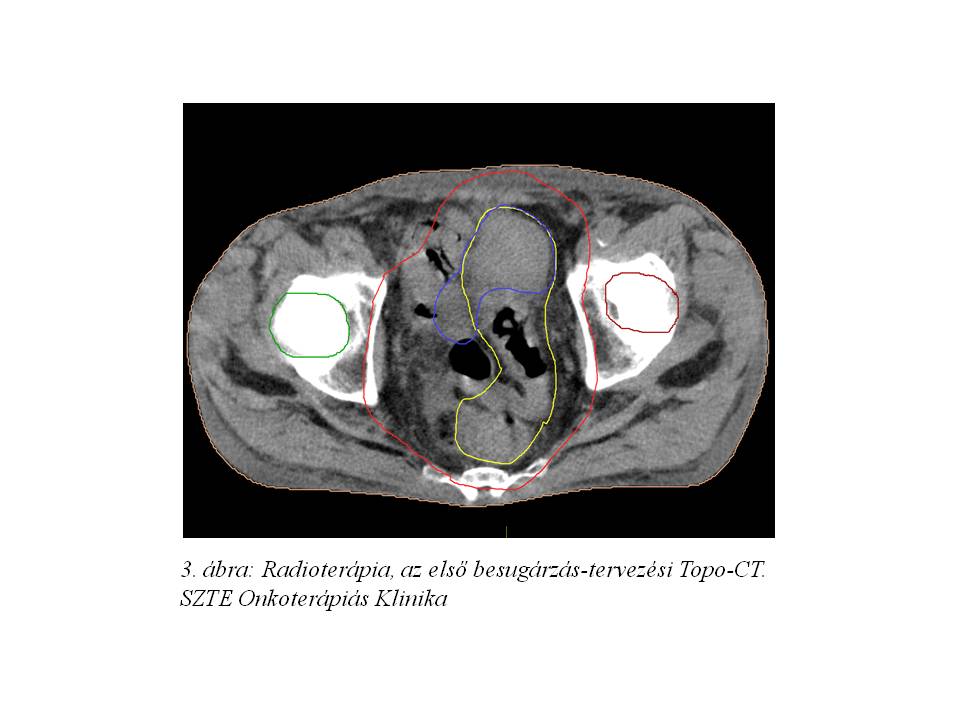

A szövettani mintavétel közepesen-jól differenciált adenocarcinomát igazolt. A képalkotó vizsgálatok alapján regionális, illetve PAO régióban detektálható lymphadenomegalia is igazolódott (1. ábra, 2. ábra).Stagingmellkas CT vizsgálat tüdőáttétet nem igazolt, tumor marker vizsgálatok minimális carcino-embrionalis antigén (CEA) emelkedést mutattak (4,74 M ng/ml, norm. tartomány‹4,70). Komplett kivizsgálás alapján a daganat iniciális stadiuma T4, N1 (LYM), M1 (PAO nyirokcsomó érintettség) lett definiálva, mely miatt, onkoteam döntés alapján, neoadjuváns kemoradioterápia indult 2014. júniusában (3. ábra, 4 ábra). A radioterápia indításától kezdve folyamatos compliance problémák nehezítették a kezelést. A beteg a szükséges kontrollvizsgálatokon nem vett részt, GI és vizeletürítési panaszaival SBO-n, sebészeti és urológiai ambulancián jelent meg, mely miatt sugárkezelését 11 frakció (19,8 Gy) leadását követően felfüggeszteni kényszerültünk. A beteg a sugárérzékenyítő, orális capecitabine (Coloxet, 825 mg/m2) citosztatikumot is csupán 1 hétig szedte. A fokozódó subileusos panaszok miatt urgens, székletpasszázst biztosító deviáló tranversostoma képzés történt SZTE Szebészeti Klinikán.